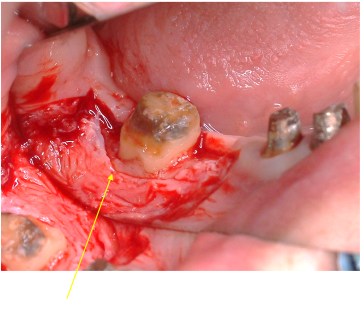

歯肉形成外科の術中所見です。最終的は被せもののイメージを行いながら歯茎と顎の骨の整形を行いました。

歯茎の下の方まで虫歯でしたが歯茎の上までしっかりと健康な歯の部分を出すことができました。